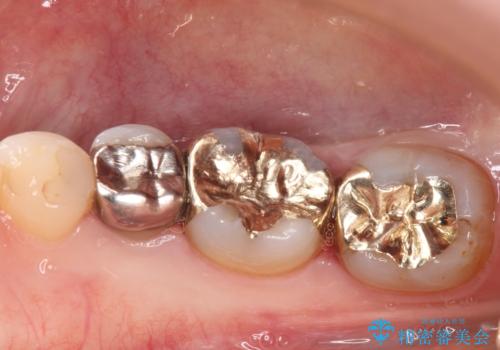

下の奥歯の虫歯をゴールドインレーで治療

ゴールドインレーは適合がよいため、虫歯の再発のリスクが少ない非常に優れた材料です。

ゴールドインレーはセラミックインレーと比べ、割れるリスクが低いため、咬合力が強い方にお勧めです。